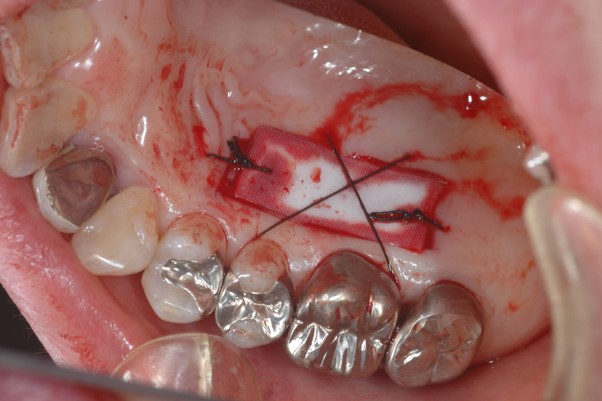

下写真をご覧ください。

そこで、下写真のようにインプラント治療を行う前に、口蓋より角化歯肉(粘膜)を移植して環境を整えました。口蓋にはコラーゲンを移植して創傷部をカバーしています。